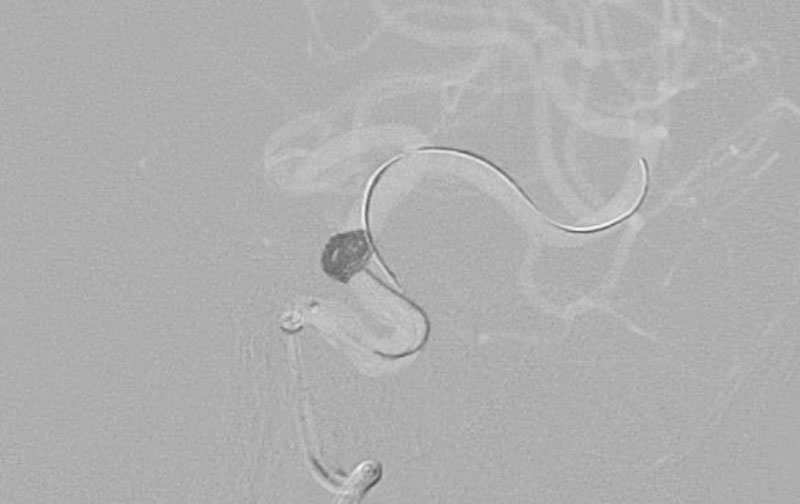

No.1631 手術前

No.1631 手術中

No.1631 手術後